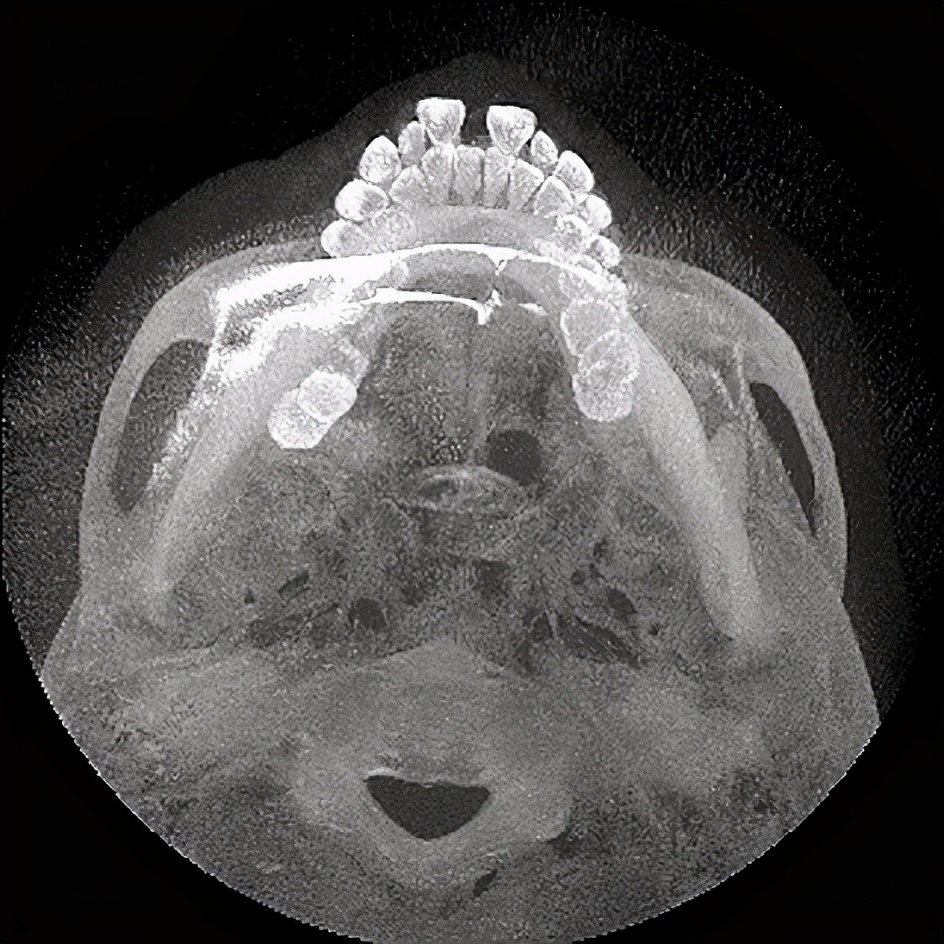

【术前全景片/CBCT】

术前全景片